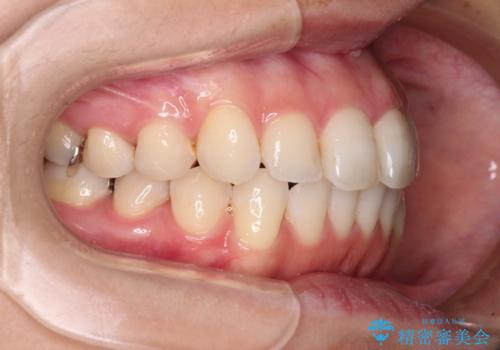

【モニター】前歯のデコボコをインビザラインできれいに整える

- 前歯のデコボコを気にして来院された患者様です。

主に下顎歯列全体の後方移動とIPR(歯と歯の間を削る)によってデコボコが解消するように設計し、インビザラインにより治療を行うこととしました。

舌突出癖がある方ですと、叢生が解消すると同時に前方に拡大されてしまいますが、ゴムかけをしっかりと行ってくださったこともあり、スッキリとした仕上がりとなりました。